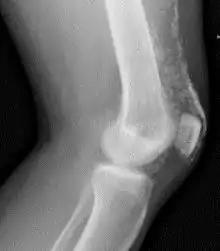

X-Ray of the knee in a person with dermatomyositis.

Magnetic resonance imaging may be useful to guide muscle biopsy and to investigate involvement of internal organs;[14] X-ray may be used to investigate joint involvement and calcifications.[15]